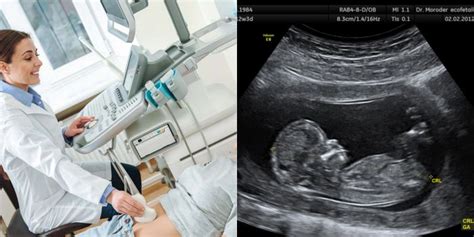

Prieš nėštumo nutraukimą gydytojas atlieka apžiūrą, patikslina nėštumo trukmę, įvertina moters sveikatos būklę, paskiria reikalingus laboratorinius ir instrumentinius tyrimus. Nėštumo laikas yra apskaičiuojamas pagal moters paskutinių mėnesinių datą, jei mėnesinių ciklas buvo reguliarus, arba ultragarsinio tyrimo metodu, jei mėnesinių ciklas buvo nereguliarus arba moteris tiksliai neprisimena paskutinių mėnesinių datos. Visi reikalingi tyrimai dažnai atliekami vietoje, o atsakymai gaunami iš karto konsultacijos metu.

Kai nėštumas nutraukiamas dėl medicininių indikacijų antrajame trimestre (iki beveik 22-osios savaitės), procedūra skiriasi nuo ankstyvųjų nėštumo nutraukimo metodų. Nėštumui nutraukti paskiriama data, numatytu laiku reikia atvykti į ligoninę. Pacientei atvykus pirmiausia atliekamas ultragarsinis tyrimas, kraujo tyrimai.